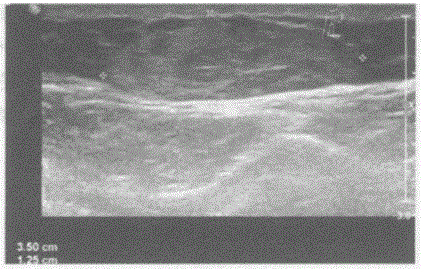

问题 临床资料:女,49岁,自述腹壁摸到多个肿物。 临床物理检查:皮下可扪及多个结节,边界清晰,无压痛。 超声综合描述:腹壁皮下脂肪层内可见数个长圆形中等回声区,最大5.5cm×2.3cm,长径与厚度比值>2,内回声欠均,包膜完整,探头加压轻度变扁。 超声提示:

选项 A.腹壁皮下脂肪瘤 B.腹壁血管瘤 C.腹壁纤维瘤 D.腹壁正常皮下脂肪组织声像图

答案 A